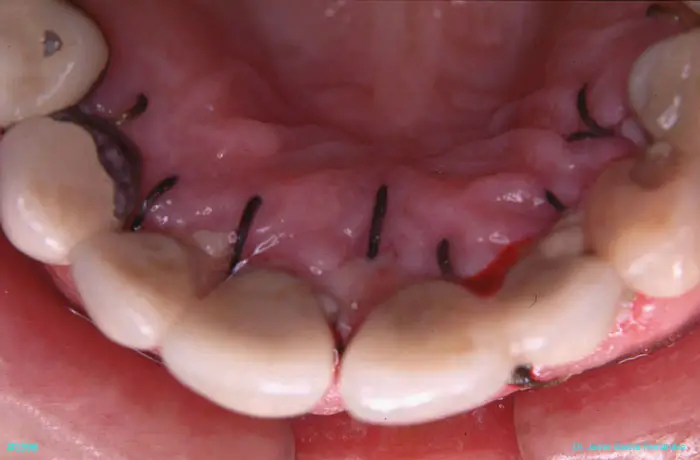

Atlas of Surgical Techniques in Periodontics. Chapter III. Atlas de Técnicas Quirúrgicas en Periodoncia